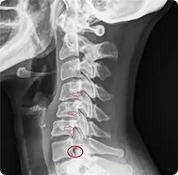

從你的X光片看出頸椎有顯著的變形,關節間隙狹窄,並且椎體錯位,這可能是導致神經受到壓迫的原因。

自律神經失調與交感神經過強

在頸椎病患者中,交感神經的過度活躍會讓人處於持續的緊張狀態,影響身體各部位的正常運作,尤其是頸部、肩膀背部肌肉變得僵硬。同時,腦脊髓液的循環受到阻礙,這可能導致流入耳部,引發眩暈或耳鳴等症狀。